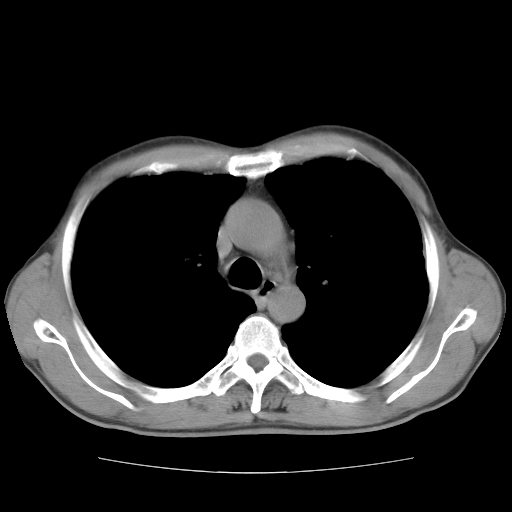

以下是引用drzhang8888在2008-11-20 22:20:00的发言:[br]密集的短毛刺,血管集束,胸膜凹陷,周边型肺癌可能性大,另双肺多发磨玻璃影,考虑感染

以下是引用流浪星在2008-11-20 22:28:00的发言:[br]左肺上叶近外围区见一类圆形结节影,毛刺征、胸膜尾征阳性,临近肺组织见多发渗出灶。考虑1,炎症性病变。 2.周围性肺癌。建议抗炎治疗后复查。